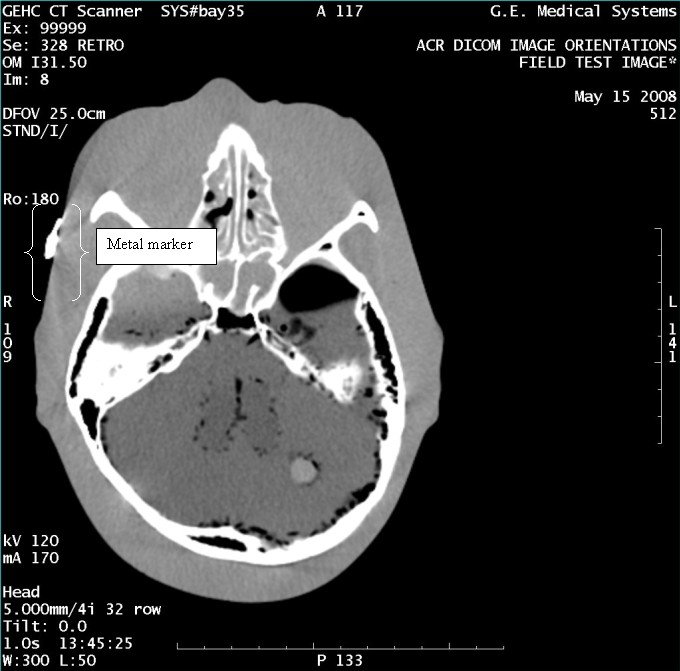

- With the support of the site personnel, examine the images sent

to the Review Station (i.e., 12 series, each with 1 image) and compare

their orientation to the images in this document.

- Each image contains a metal marker on the phantom's right cheek.

- Each image in this document contains a description of the expected

orientation of the metal marker (i.e. to prove Left and Right) as

well as the Posterior and Anterior orientation description.note:

The sample images included in this document use “R”, “L”, “P”, and “A” for “Right”, “Left”, “Posterior” and “Anterior” orientation. The Hospital Review Station may use a different style of annotation. The style used is not relevant to this procedure.

Figure 7. Exam 99999, Series 328